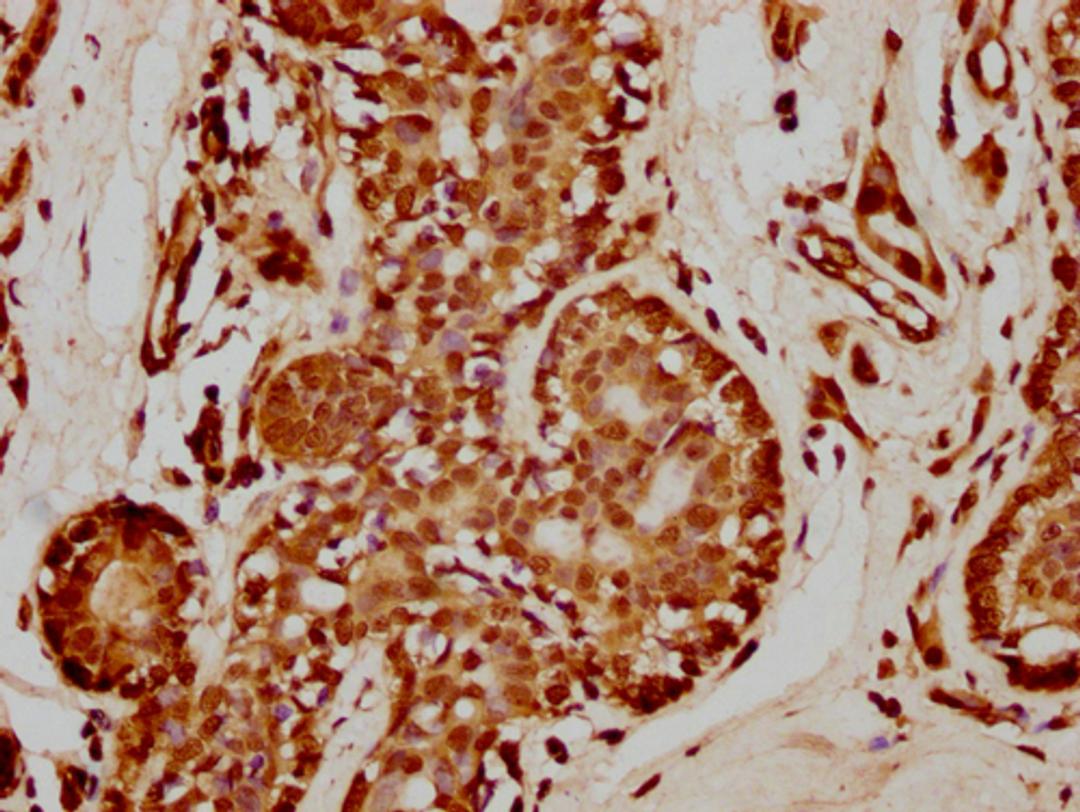

IHC image of CSB-PA010429PA35nme1HU diluted at 1:50 and staining in paraffin-embedded human breast cancer performed on a Leica BondTM system. After dewaxing and hydration, antigen retrieval was mediated by high pressure in a citrate buffer (pH 6.0). Section was blocked with 10% normal goat serum 30min at RT. Then primary antibody (1% BSA) was incubated at 4°C overnight. The primary is detected by a biotinylated secondary antibody and visualized using an HRP conjugated SP system.